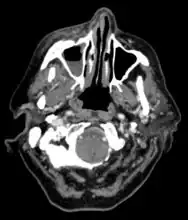

Imaging

Imaging is often performed, such as CT scan of lungs and sinuses.[38] Signs on chest CT scans, such as nodules, cavities, halo signs, pleural effusion and wedge-shaped shadows, showing invasion of blood vessels may suggest a fungal infection, but does not confirm mucormycosis.[16] A reverse halo sign in a person with a blood cancer and low neutrophil count, is highly suggestive of mucormycosis.[16] CT scan images of mucormycosis can be useful to distinguish mucormycosis of the orbit and cellulitis of the orbit, but imaging may look identical to those of aspergillosis.[16] MRI may also be useful.[39]

CT head (axial): invasion of right maxillary sinus (presented with double vision, swollen painful eye).

CT head (coronal) of same person.